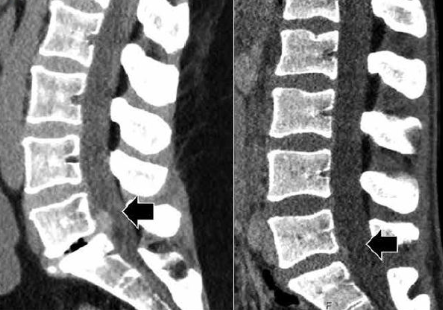

CT(전산화 단층촬영): 추간판 및 신경 압박 정도 등 협착의 위치와 원인 파악에 도움.